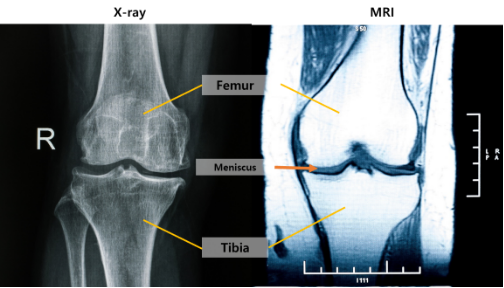

[From left] X-ray and MRI images of the knee

In the early stages of knee OA, pathological changes occur first in soft tissues, such as articular cartilage and the meniscus. However, X-ray—the most commonly used diagnostic tool—has limited sensitivity for detecting these early changes. Although MRI allows detailed evaluation of soft tissues, its accessibility is limited, and few longitudinal studies have systematically examined the relationship between MRI and X-ray findings over time.

The analysis revealed that the earliest structural change in knee OA was cartilage loss in the central femoral region. Notably, this finding was already evident in Kellgren–Lawrence grade 0 knees, which are considered normal on X-ray, demonstrating that MRI is a critical tool for detecting early osteoarthritic changes.